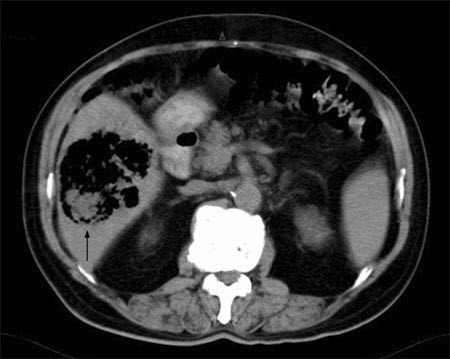

Abscesso hepático: tomografia computadorizada (TC) mostrando um cisto equinocócico rompido e infectado de 8 cm por 8 cm e um cisto equinocócico de 4 cm por 4 cm em um homem de 69 anos de idade, que apresentou hipotensão e dor torácica com irradiação para a região epigástrica

Do acervo de imagens radiológicas do Massachusetts General Hospital (MGH)